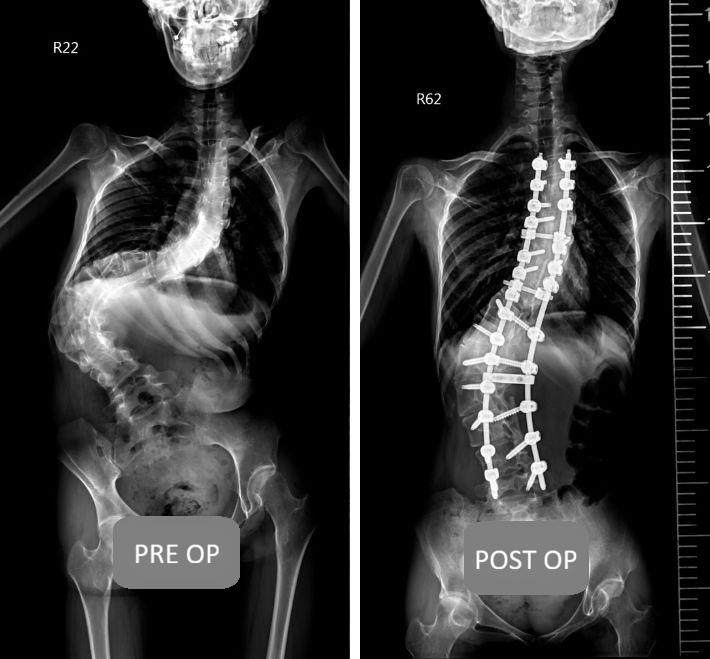

The Complete Guide to Scoliosis Surgery: From the Golden Window of Treatment to Minimally Invasive Techniques — A Surgeon’s Explanation of Key Factors for Safe Correction

Is surgery always necessary for scoliosis? Dr. Chien‑Chun Chang provides an in‑depth analysis of surgical indications for adolescents and adults. With the introduction of the O‑arm 3D navigation system, surgical error is reduced to under 0.1 cm, significantly enhancing safety. This article details minimally invasive procedures, implant costs, recovery timelines, and frequently asked questions about postoperative exercise — helping you reclaim an upright, confident life through precision medicine.